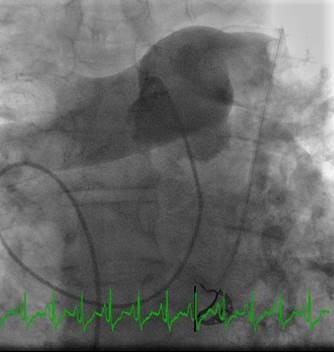

Paciente con hemorragia gastrointestinal activa que impide el uso de trombolíticos. Angiografía de la arteria pulmonar principal (más selectiva a la derecha) realizada con un catéter en espiral de 6 F en ángulo, que muestra la presencia de un trombo de gran tamaño dentro de las arterias pulmonares izquierda y derecha, y en las respectivas bifurcaciones lobares.

Se efectuó una trombectomía reolítica con el catéter PE de AngioJet® a través de una guía de angioplastia hidrófila de 0,035’’, partiendo de la arteria pulmonar izquierda y la bifurcación lobular inferior. La intervención se repitió en la arteria pulmonar derecha y en las bifurcaciones lobulares correspondientes. La intervención se detuvo debido a una bradiarritmia. Además, el tiempo de activación total se encontraba cerca del  límite recomendado (4 minutos).

A pesar del gran volumen de trombo eliminado, el angiograma final solo muestra una leve mejora de la obstrucción. Sin embargo, el objetivo del tratamiento es simplemente restaurar el flujo y no eliminar el trombo por completo, ya que incluso el modesto resultado de este angiograma estuvo acompañado de una considerable recuperación hemodinámica y de intercambio gaseoso.